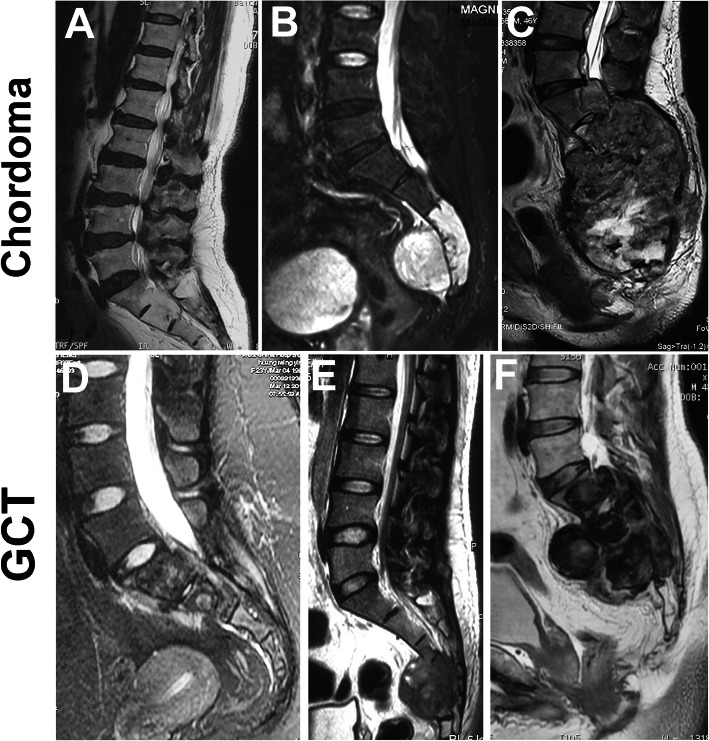

To distinguish the high or low level was more important for the design of surgical strategy. Thus, we analyzed the location distribution of all tumors. For the malignant tumors, 412 were located at the region of above S3 and 304 tumors were at the S3/below S3. For the benign tumors, 485 were located at the region of above S3 and 184 tumors were at the S3/below S3. Chordoma and giant cell tumors are the top two histologic types of tumors at the sacrum. Among 316 cases with chordoma, only five (1.6%, 5/316) were located at Region S1 to S2, 145 (45.9%, 145/316) being at Region S3 and below S3 and 166 (52.5%, 166/316) were associated with both two regions. Meanwhile, among 205 cases with giant cell tumor, eighty tumors (39%, 80/205) were located at Region S1 to S2 and 114 (55.6%, 114/205) cases were associated with both two regions. Only eleven giant cell tumors were located at Region S3 and below S3. Notably, there was a significant difference in location distribution between chordoma and giant cell tumor (Table 7). We showed typical cases with chordoma and giant cell tumor in different regions of the sacrum (Fig. 5). Chordoma usually originated at the low level of the sacrum and extended upward and forward. Giant cell tumor often stemmed from the high level of the sacrum and destroyed the lower level. This characteristic was more useful to distinguish chordoma from the giant cell tumor.

Fig. 5.

Location distribution of chordoma and giant cell tumor. a Chordomas at the Region S1 or S2 or S1-2 accounting for 1.6% (5/316); b Chordomas at the Region S3 or below S3 accounting for 45.9% (145/316); c Chordomas associated with both high and low levels accounting for 52.5% (166/316); d GCT at the Region S1 or S2 or S1-2 accounting for 39.0% (80/205); e GCT at the Region S3 or below S3 accounting for 5.4% (11/205); f GCT associated with both high and low levels accounting for 55.6% (114/205)